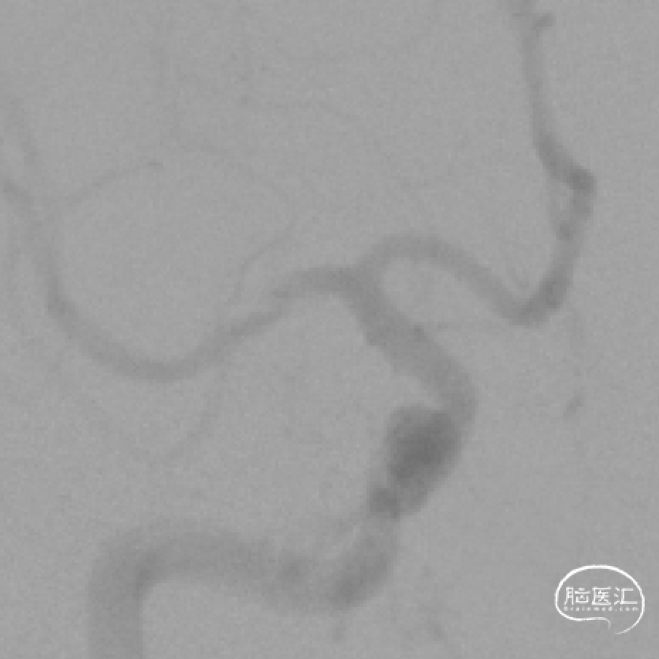

术前DSA示:右侧大脑中动脉重度狭窄,无颅内出血,参考血管直径为2.22mm,靶病变长度为3.47mm,靶病变直径狭窄程度(WASID法)88%。

灌注导管沿微导丝送入,路图下送至M2段后撤出微导丝,赛诺神畅 2.5-15mm COMETIU™自膨式颅内药物涂层支架系统沿微导管送入,于病变部位定位准确后释放支架,透视下见支架位置准确,贴壁良好,复查造影见病变管腔明显恢复,残余狭窄约10%,血流通畅,分支显影良好,未见造影剂外渗。撤出支架输送系统。

2023-06-20复查脑血管造影示:右侧大脑中动脉狭窄支架术后,支架在位,形态良好,未见再狭窄。

2024-06-13复查脑血管造影示:右侧大脑中动脉支架术后,管腔内通畅。